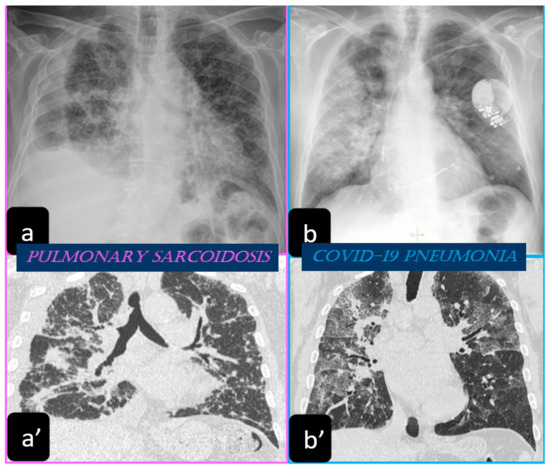

2.1. Imaging Findings of Sarcoidosis. The Scadding Classification at the Chest X-ray

2.2. Typical and Atypical Manifestation of Pulmonary Sarcoidosis at HRCT

3.1. Chest X-ray Findings

3.2. HRCT Findings of Lung Involvement from COVID-19